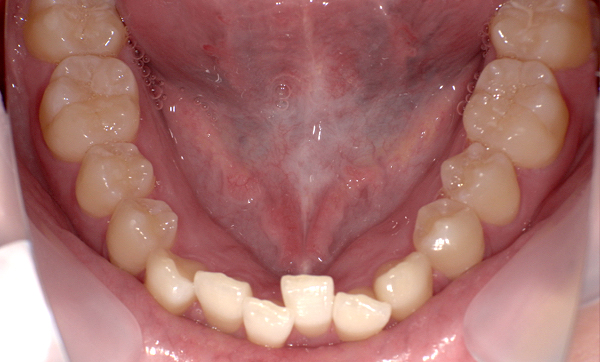

症例_009 「上下の前歯」症例

治療期間:7ヶ月金額:54万円+税20代女性捻転歯一部の反対咬合前歯のガタガタ